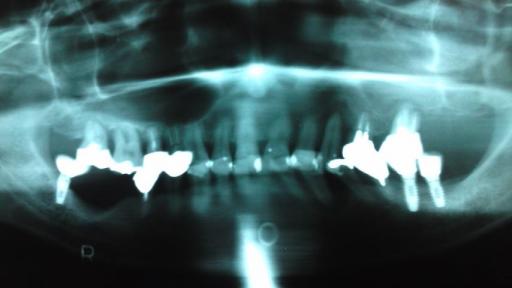

インプラントによる噛み合わせ構築法

奥歯で 全く噛めていませんでした。

左上の奥歯に3本 インプラントの土台が入りました。

左の奥歯が噛めるようになりました。 続いて 右下に2本のインプラントの土台が入りました。